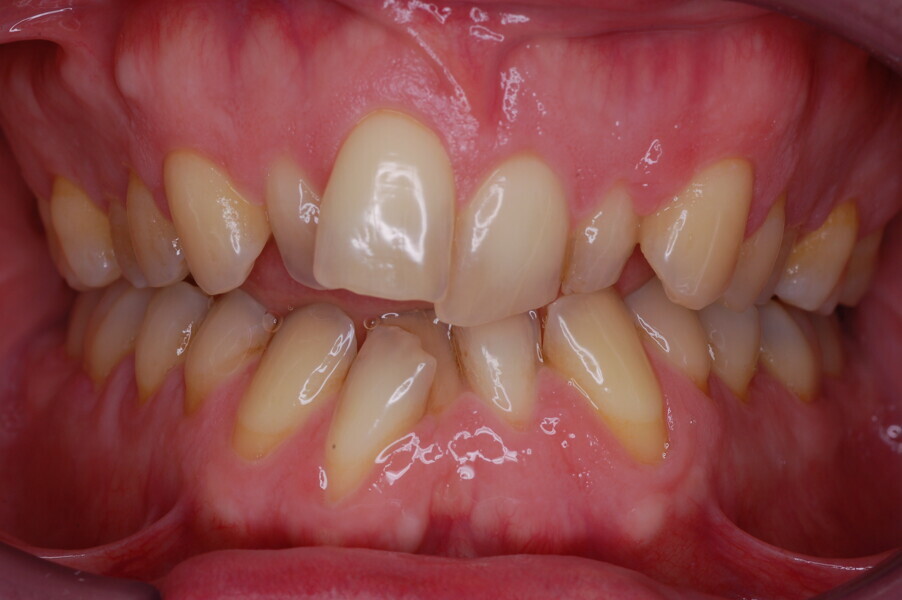

A healthy 39-year-old man presented to our orthodontic office with the chief complaint of an unattractive dental appearance and fear of the orthognathic surgery proposed by another orthodontist. Clinically, the patient’s profile was straight, and the frontal view did not show any facial asymmetry. The functional examination did not reveal any mandibular deviation or reduced movements. The patient had no joint pain, and no joint noise was observed.

Figs. 1–8: Pretreatment facial and intra-oral photographs.

From the periodontal point of view, the patient showed a good attitude to oral hygiene, but crowding of the mandibular incisors made cleaning difficult in that area, causing plaque accumulation and localised gingival inflammation. The panoramic radiograph revealed the presence of the mandibular third molars and confirmed the absence of the mandibular right central incisor (Fig. 10).

The cephalometric analysis showed a skeletal Class II malocclusion (convexity of Point A: 4.9 mm), a slightly retruded chin position (facial depth: 78.1°) and a skeletal open bite tendency (lower facial height: 53.19°; facial axis: 80.58°; Fig. 9). The mandibular incisors were lingually tipped (Li–APog: 9.3°) and retruded (Li–APog: 1.55 mm), and there was an increased inter-incisal angle of 142.9°.